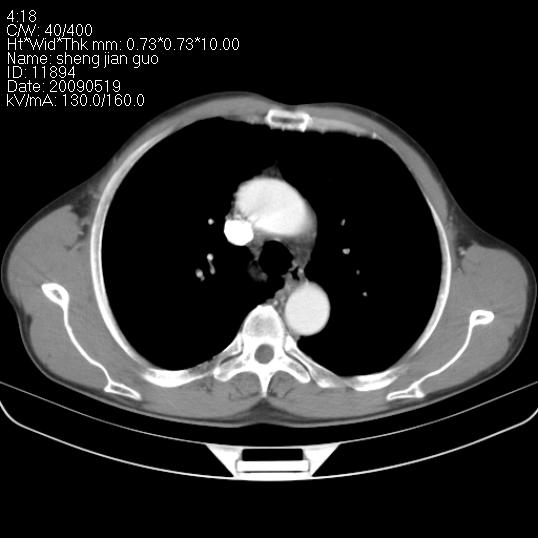

以下是引用zjzjr在2009-5-19 17:25:00的发言:[br]支持楼主考虑,另左肺下叶阻塞性炎症。

以下是引用zhao_bin2008在2009-5-19 17:48:00的发言:[br]支持左肺下叶周围型肺癌并阻塞性肺炎。

以下是引用zsl6918在2009-5-20 7:10:00的发言:[br]左侧中心型肺癌!